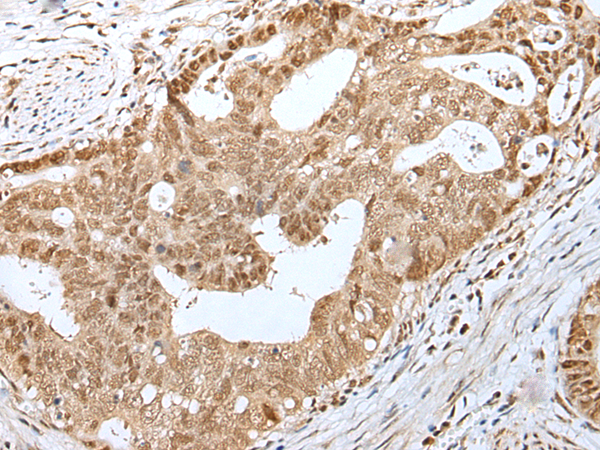

IHC positive control: |

Human gastric cancer and human tonsil |